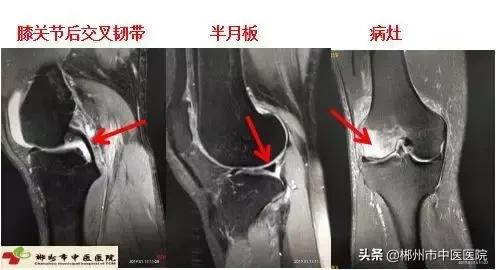

能够辅助常规X射线或CT对骨质本身病变的显示。对四肢关节、软组织及肌肉病变包括肿瘤及炎症都能清晰显示,特别是对早期急性骨髓炎,是一种灵敏度很高的检查方法。MRI也是检查膝关节半月板病变、前后交叉韧带的首选方法。如图: